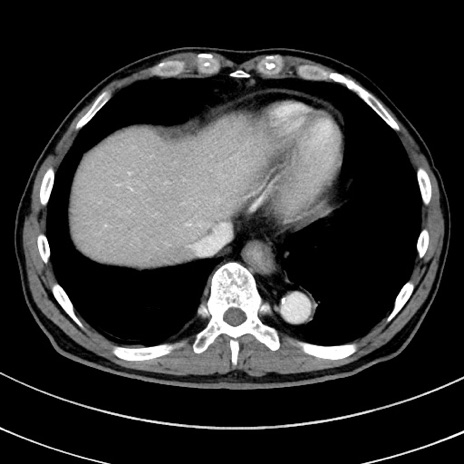

症例8(横断像)

【症例】 60歳代男性

【主訴】 黒色吐物

【現病歴】 4日前から嘔気自覚、2日前の朝食後にも嘔気あり、自分で手で嘔吐反射起こし嘔吐したところ血が混ざっていたため受診。

【既往歴】 5年前汎発性腹膜炎を伴う急性虫垂炎で手術、高血圧、前立腺肥大症、高脂血症

【身体所見】 腹部正中に手術癩痕あり 腹部平坦・軟圧痛なし膨満感あり

【データ】WBC 8400、CRP 4.54